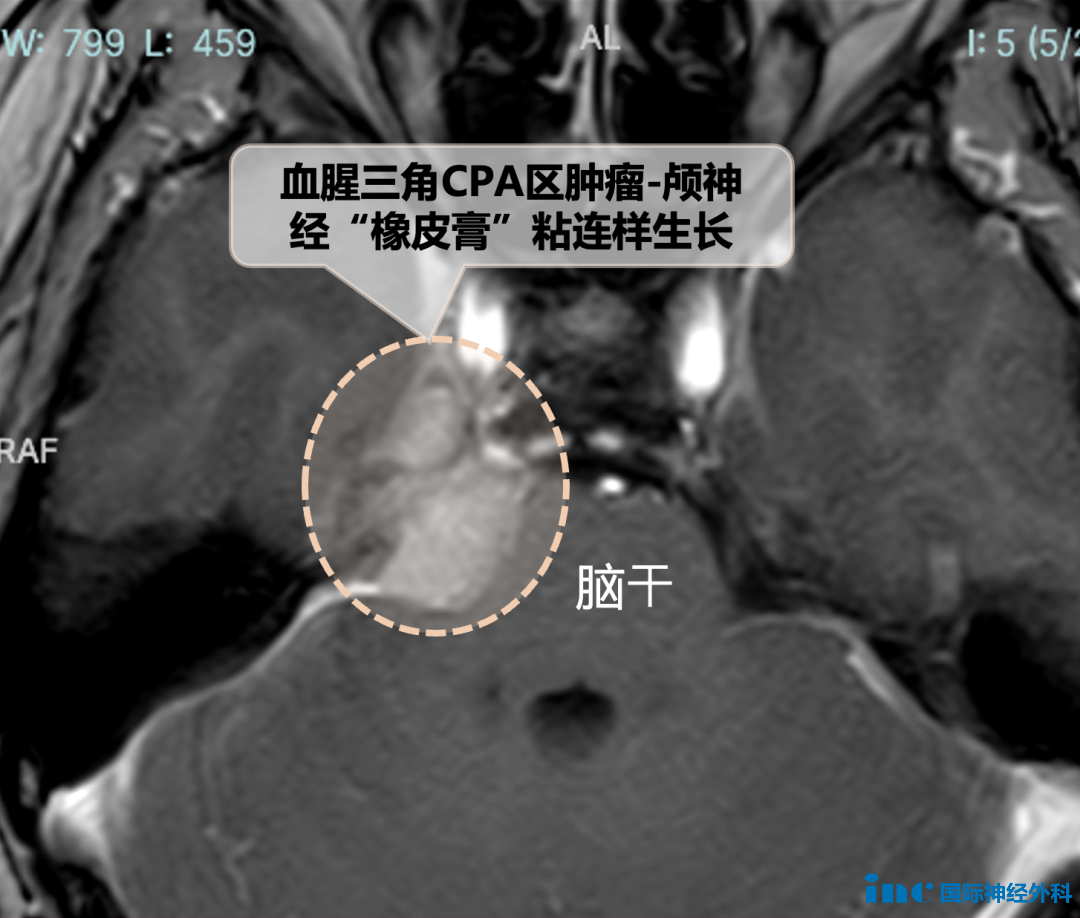

周女士脑膜瘤所在的桥小脑角(CPA)区解剖结构相当复杂,除了脑干和小脑外,还有耳蜗神经、面神经等神经穿行其间。然而,原本就是高难度的手术却更加棘手——肿瘤已经跟周围的神经血管粘在了一起,比之前预估的复杂得多。因为这些“缠绕”在一起的组织,光靠术前的影像检查(比如CT或MRI)是看不清楚的,只能在打开脑袋后才能“见真章”。

周女士的肿瘤与滑车神经,高度黏连,这是第四条 (CN IV)颅神经,也是最细的颅神经。支配眼球内旋,其受损可引起眼球运动障碍,同时因看不清物体,就会通过歪头或者斜颈代偿,以减轻复视影响。

滑车神经和肿瘤紧紧黏在一起。为了把它们分开,巴教授足足花了1.5个小时解决,像拆胶带一样小心翼翼地操作着。接下来,三叉神经也不甘示弱,跟肿瘤抱在一起,像是死党一般。巴教授最终也在神经电生理监测的监测下慢慢拆解、剥离肿瘤。保护了这些重要颅神经,还完成了肿瘤全切!

对于很多患者来说,体检发现脑瘤往往如同晴天霹雳。但事实上,早期发现、尽早治疗恰恰是最大的幸运。就像周女士的案例,这个“安静”的脑膜瘤,术中竟发现已经与周围的神经血管形成了紧密粘连,这个“变数”让手术难度大大增加。

现代影像学技术(比如CT或MRI)虽能发现肿瘤,却难以完全呈现这些细微的粘连关系。只有在手术显微镜下,才能看清这些错综复杂的“生命线”。值得庆幸的是,由于发现及时,即便肿瘤已经形成粘连,仍在国际神外大咖巴教授可成功手术的范围内。